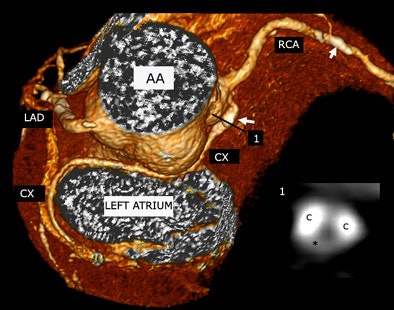

| Plaque type 2 (mixed, predominantly calcifying) in a 72-year-old man with stable angina pectoris was found in an aberrant circumflex (CX) arising from right coronary (RCA) ostium and coursing between ascending aorta (AA) and left atrium (LA) distally. The inlay (1) shows a cross-sectional slice of the proximal CX plaque, white arrow is pointing at calcification. A small noncalcifying plaque component (hypodense) was found between two calcifying plaque (C) components. All images courtesy of Dr. Gudrun Maria Feuchtner. |